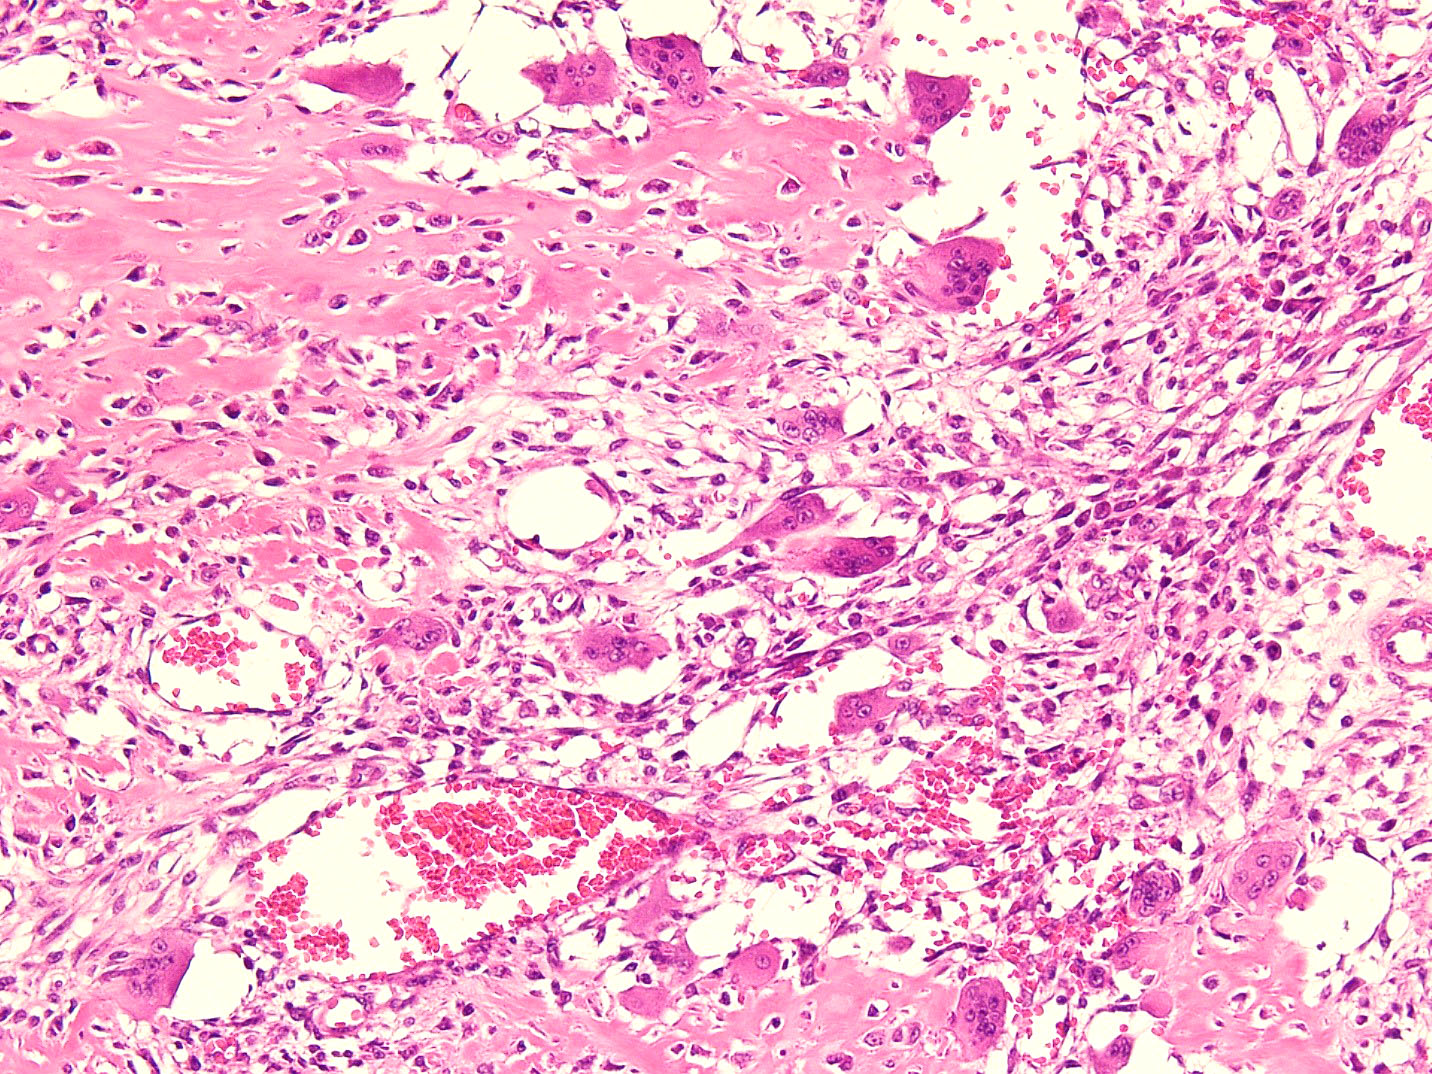

- Intermediate zone:

- There is a mixture of fibroblasts and osteoblasts along with erratic osteoid separated by small sized vessels

- Scattered chondrocytes may be appreciated

- Peripheral zone:

- Osteoid undergoes calcification and leads to lamellar bone formation

- Islands of mature or immature cartilage may be present

- Extreme periphery / margin shows mature bone with osteoblastic rimming and little to no pleomorphism

- Lesion is separated from the normal tissue (muscle) by a zone of loose, myxoid fibrous tissue

Microscopic (histologic) images